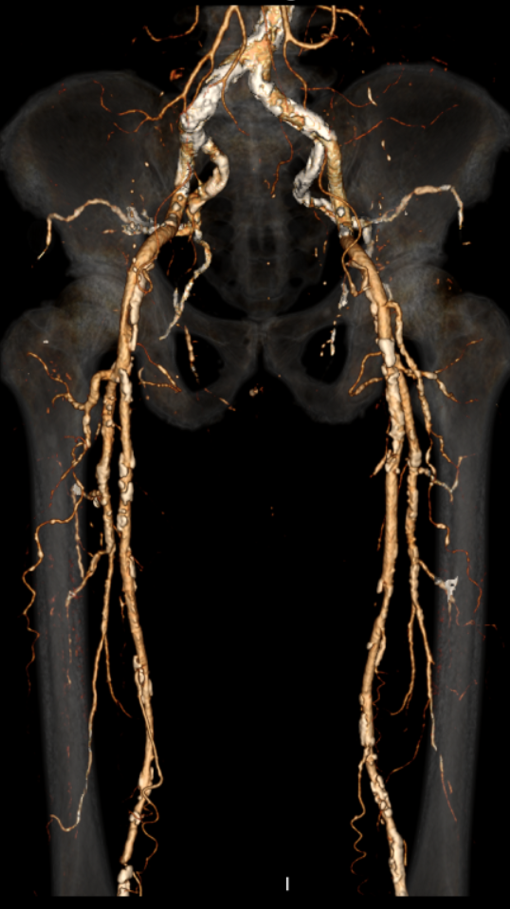

中山大学附属第一医院血管外科姚陈主任团队成功运用LiqMagic?P18外周血管内冲击波导管治疗一例下肢动脉硬化闭塞症患者。该患者为一名老年男性,患高血压和糖尿病20多年,并伴有慢性肾功能不全。因右脚持续疼痛1年多入院接受治疗。术前造影结果显示下肢多发动脉钙化,其中右侧股浅动脉、腘动脉、胫前动脉、足背动脉重度狭窄,并局部闭塞。

▲患者术前CTA